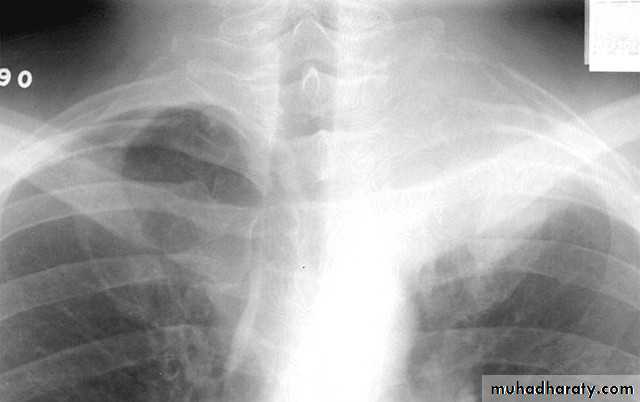

Klebsiella pn. Massive pn.